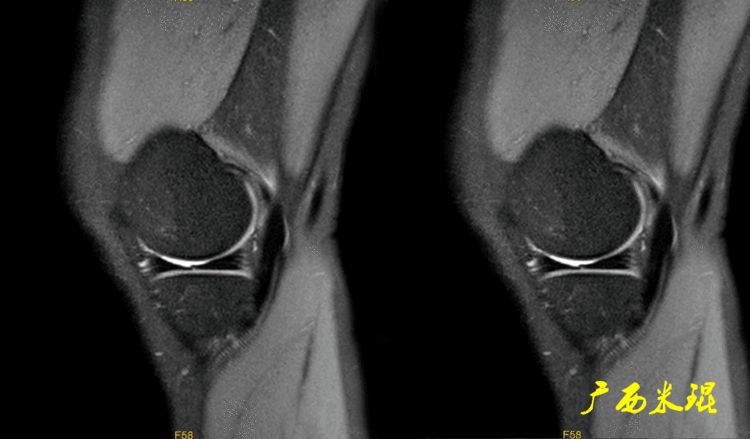

下面这张MR矢状位显示为类似双后交叉征,后交叉韧带前下方的低信号其实是正常的外侧半月板后角,半月板桶柄状撕裂多发生于内侧,绝大多数是前交叉韧带损伤的合并伤,此病人的前交叉韧带正常,通过其他截面的半月板阅片就能排除。